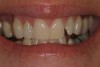

Another preparation technique is the use of air abrasion to remove the area of decay. Figure 1 shows tooth No. 19 with a sealant restoration. Using the Diagnodent, recurrent decay was detected. An air abrasion system was used to remove the old sealant restoration as well as the recurrent decay without the need for local anesthetic (Figure 2). The use of air abrasion allows for the efficient removal of the old resin material as well as the removal of the carious tooth structure.

Figure 1  An old sealant restoration with recurrent decay present.

Figure 1